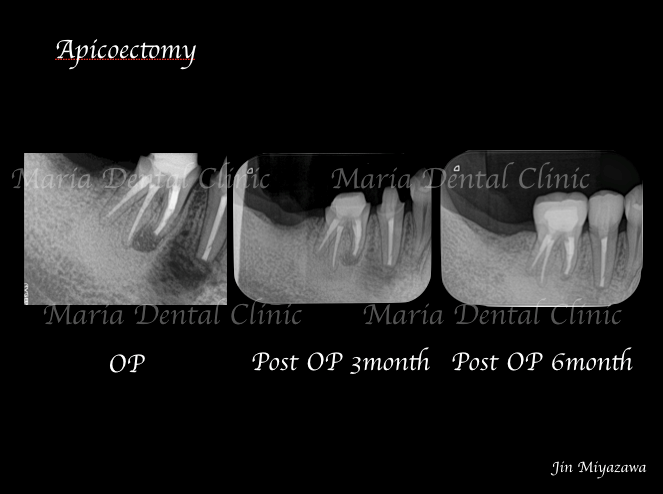

歯根端切除術症例1|術後6ヶ月で徐々に根尖透過像が縮小

のレントゲン写真を例にして見ていだければわかるように、根尖病変を除去した後6ヶ月をかけて徐々に根尖透過像(※)の縮小が確認できます。歯肉は比較的早い治癒を確認できますが、骨透過像の治癒は時間をかけてゆっくりと縮小し、半年後にはほぼ透過像の確認はできない状態まで良好な治癒を示しています。

この症例のように、定期的なレントゲン写真を撮影することで予後の変化を確実に診断できるようになります。